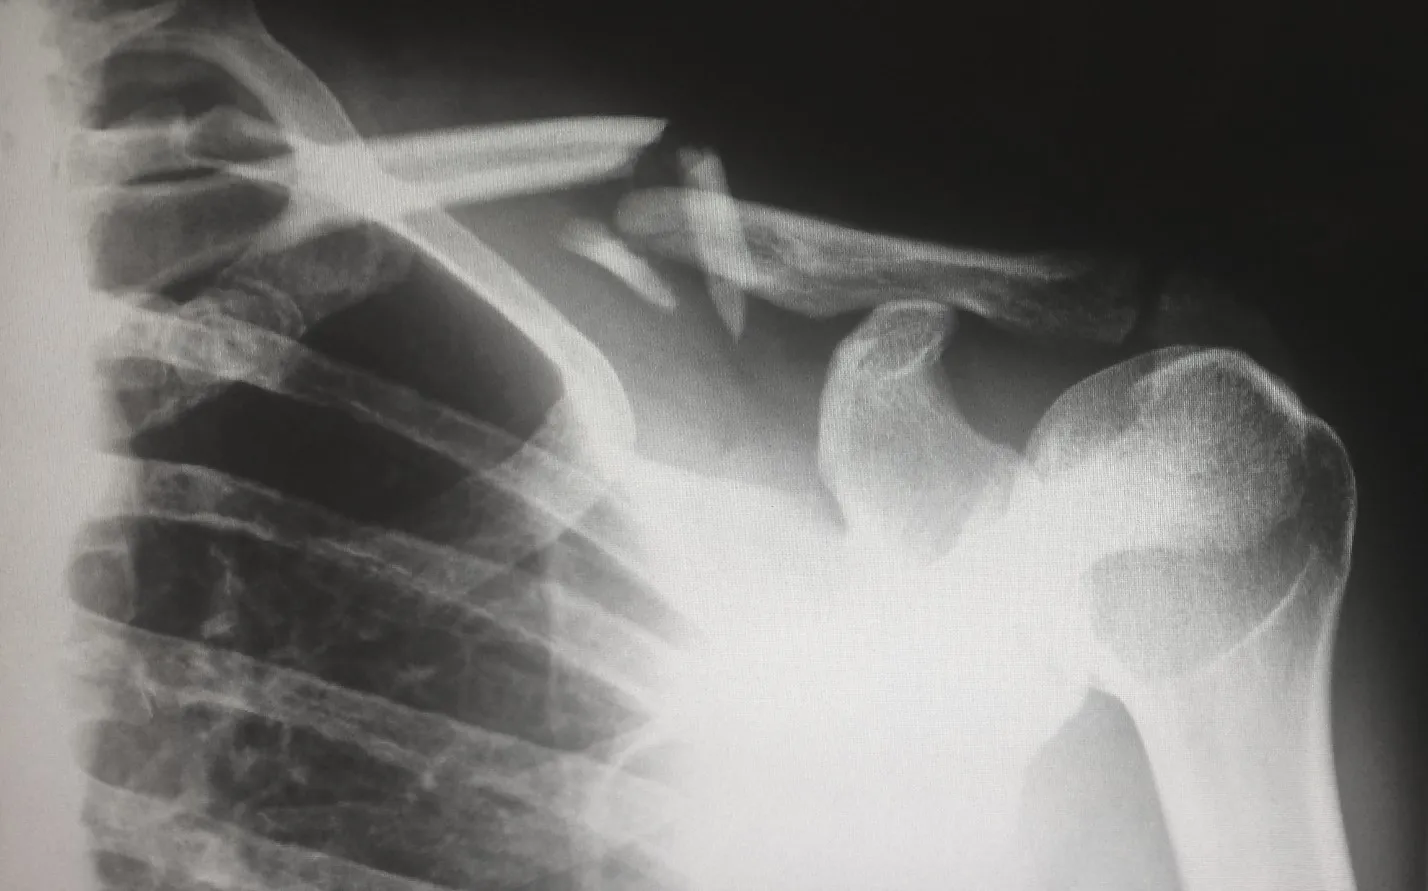

Перелом.

Сломанная кость.© pixabay.com